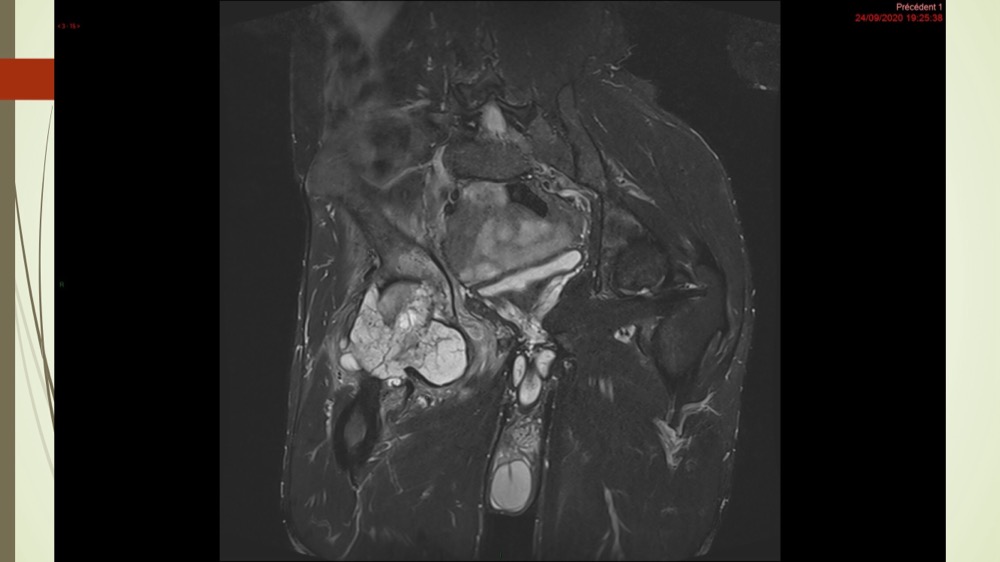

Coxalgie traînante

Kévin Mahé 29/06/2022